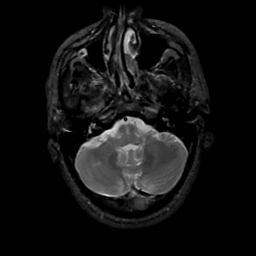

MR Study #10, April 28, 1991 -- Slice #10